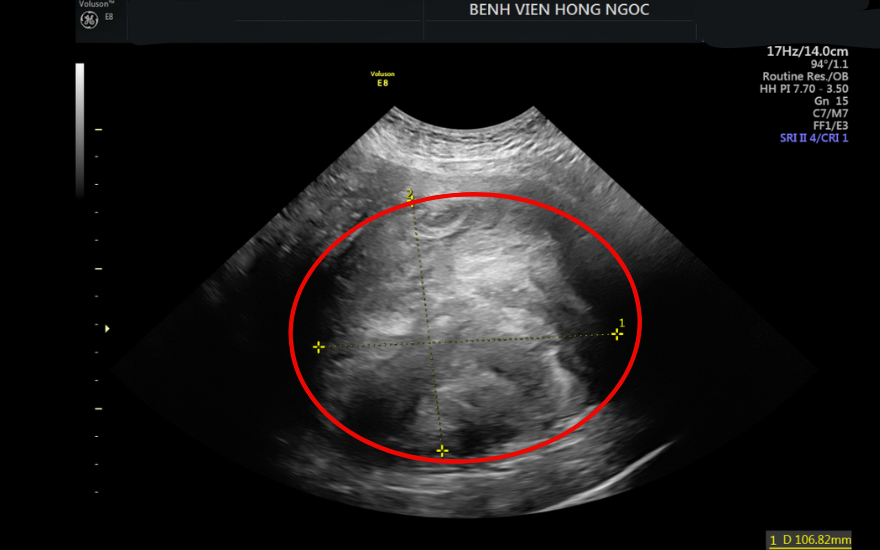

Thăm khám tại BVĐK Hồng Ngọc, các bác sĩ xác định khối u có kích thước lớn, nhiều nhánh mạch máu nuôi, xâm lấn sâu vào thành tử cung và gây chèn ép lên bàng quang và trực tràng - khiến tình trạng càng trở nên phức tạp hơn. “Nếu không phẫu thuật sớm, người bệnh có thể đối mặt với các biến chứng nguy hiểm như xuất huyết ồ ạt, hoại tử khối u do xoắn hoặc thậm chí nguy cơ chuyển sang ác tính”, ThS.BSCKII Nguyễn Văn Xuyên - Khoa Sản Phụ khoa, BV Hồng Ngọc cho biết.

Khối u có kích thước hơn 10cm choán ổ bụng và chèn vào các cơ quan lân cận.